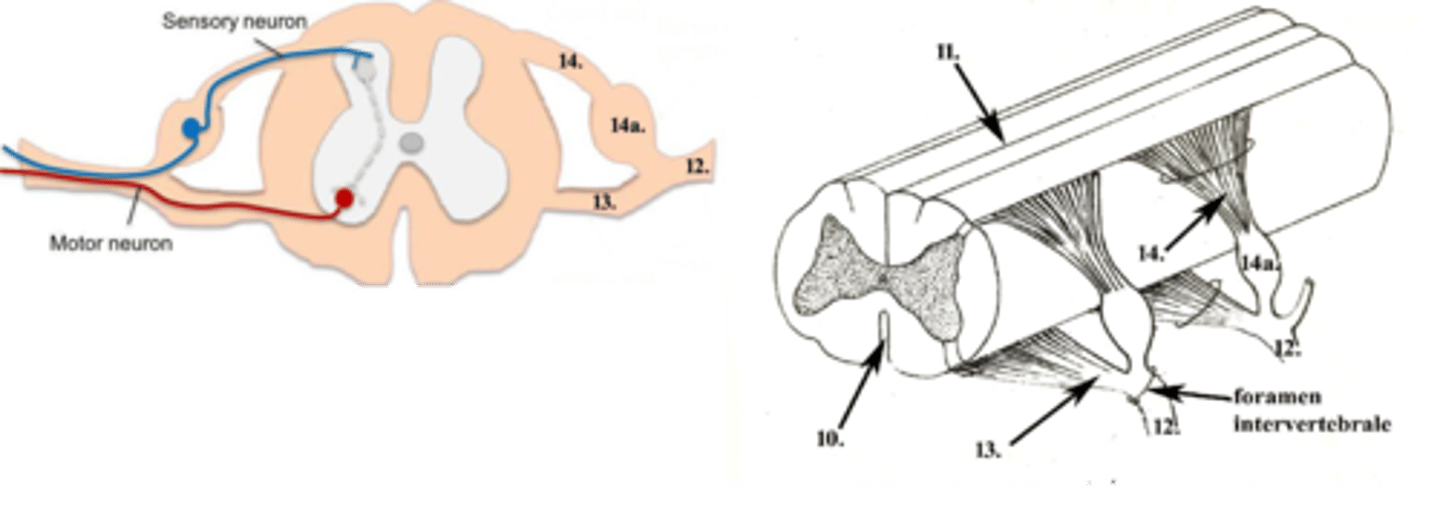

nervi spinales

12

radix ventralis

13

radix dorsalis

14

ganglion spinale

14a